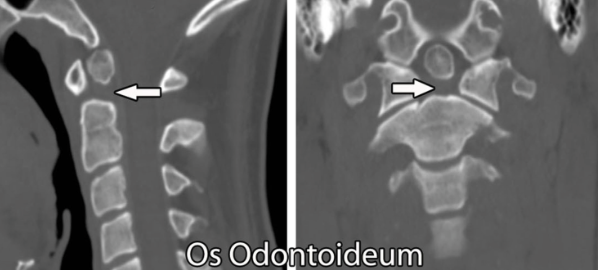

Define an odontoid fracture?

Describe the anatomy of axis?

What imaging is important in axis fx?

CT